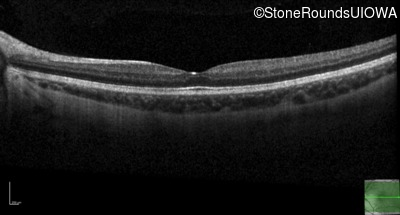

This 6 year old boy first experienced difficulty reading and seeing the blackboard at age 5.

| Age at visit: 14 years |

| Age at visit: 14 years (Visit 2) |